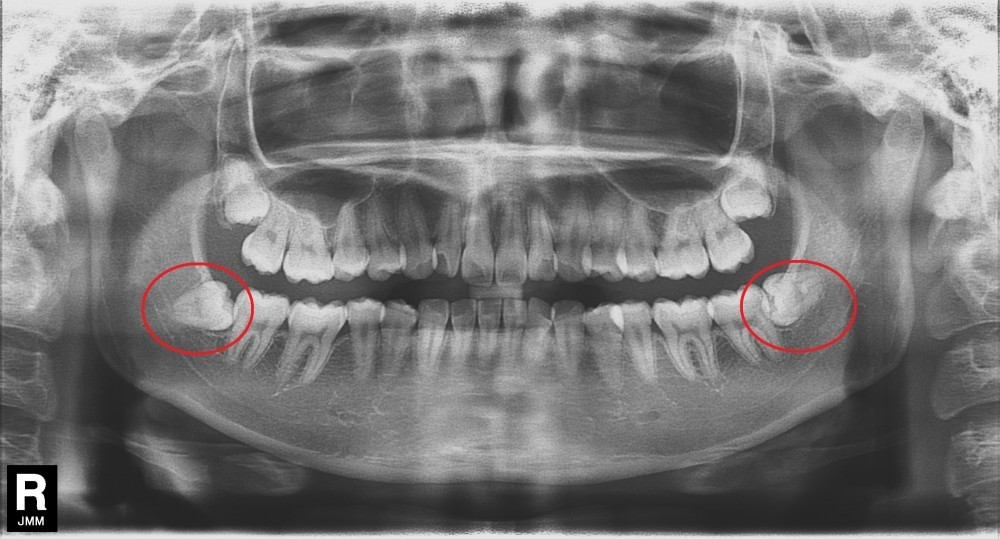

口腔外科では、親知らずの抜歯や口腔内の小外科処置など、専門性の高い治療を行っています。小禄ホワイト歯科では、特に水平埋伏智歯の抜歯に力を入れ、他の歯科医院で対応が難しい症例にも対応しています。

水平埋伏智歯は、歯が横向きに埋まっているため、下顎神経との位置関係が近く、抜歯には高い精度が求められます。小禄ホワイト歯科では3D-CTスキャンを用いた画像診断を行い、歯の根の形や湾曲の状態、下顎神経との位置関係を立体的に把握しています。その結果、より安全性を高め、短時間での抜歯につなげています。